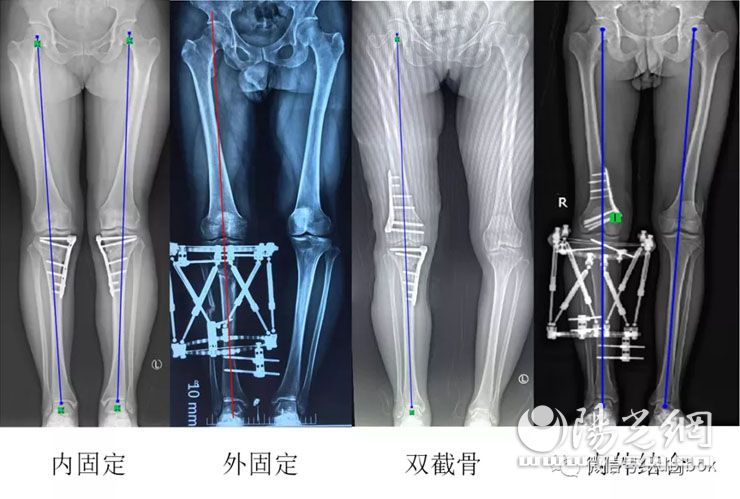

约有50%的膝关节炎患者,疼痛只局限于前内侧或内侧,往往伴有罗圈腿畸形,称之为膝关节前内侧关节炎,多数可以通过微创保膝疗法治疗。临床应用比较多的保膝疗法是单髁置换术(UKA)和胫骨高位截骨术(HTO)。这些目前都是非常成熟的手术,效果很肯定,对于畸形特别严重的,即使没有症状,也得尽早纠正,避免关节负重不平衡,造成关节过早的磨损。

第二种保膝方法是截骨术,主要针对65岁以下、相对年轻,疼痛主要在膝关节内侧,往往伴有罗圈腿畸形的患者,截骨术既能解决疼痛问题,而且对于年轻患者来讲,避免或者延迟换关节,术后还可以从事重体力和剧烈活动。

与金庸小说《天龙八部》里丐帮帮主乔峰同名的乔锋主任,医学硕士出身,工科博士。这位学霸在精准保膝方面也是绝顶高手,有着“降龙十八掌”的独家绝招和绝密武器“打狗棒”——他独创设计的截骨术前测量方法,是目前国际上最精确的术前测量方法,术中无需透视力线,即可获得良好的力线矫正,精准快速;自主发明并申请专利的闭合截骨导向器,被同行称为“截骨神器”,被国内外200多家医院广泛使用;撑开截骨导向器,自带7°后倾,能够快速准确置入导致,更好的保留合页,;自主设计的数字六轴外固定架,无论复位精度、固定效果、操作便捷与学习曲线等方面,均明显优于泰勒架(泰勒架被称为全世界最先进的骨科外固定架);自主设计的3D打印骨科外固定架,具有自动复位骨折功能,而且可以精确控制骨折处的力学环境和固定方式,手术时间不到1.5分钟,术中无需透视,操作简单,术后即可下地行走,居世界领先地位。